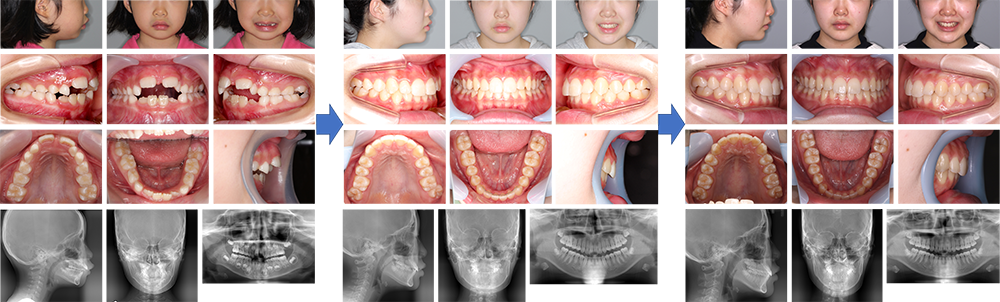

【治療例 K6440】初診時年齢:9歳4か月 / 性別:女性 / 主訴:上の歯が変な所から生えてきている、下の歯が生えてくるスペースが無い

治療の概要:上顎両側第一小臼歯の萌出位置の異常を主訴に来院されたが、下顎骨が後退しており、下顎前歯部は上顎前歯部の舌側歯肉を咬んでいた。まず第一乳臼歯を抜去し第一小臼歯の萌出を促した。咬合斜面板にて下顎骨の前方移動を図りつつサービカルヘッドギアと2×4装置で上顎前歯部の歯列の改善と側方歯群のスペース確保に努めた。その結果、小臼歯非抜歯にて治療を終えることができ、綺麗な側貌と緊密な咬合を獲得することができた。

主訴:上の歯が変な所から生えてきている、下の歯が生えてくるスペースが無い

診断名:下顎が後退した上顎前突症例

使用した主な装置:咬合斜面板、サービカルヘットギア、リップバンパー、マルチブラケット装置、歯肉切除

抜歯/非抜歯および抜歯部位:非抜歯

※こちらの症例は2016年9月から2024年3月に行った矯正治療です(2020年11月~は保定期間)

治療期間:7年6か月

治療回数:54回